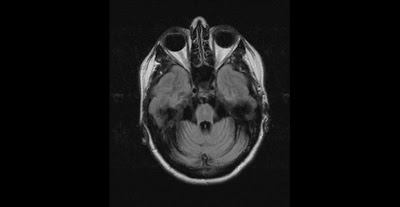

Olivopontocerebellar atrophy (OPCA)

This is MRI of a 50 year old female with Family history of Olivopontocerebellar atrophy in father. She has been suffering from ataxias and falls for 3 years. On exam demonstrate dysmetric finger to nose and heel to shin, has hypo metric saccades , mild ocular apraxia . There is lack of Bulbar weakness or other parkinsonism features.